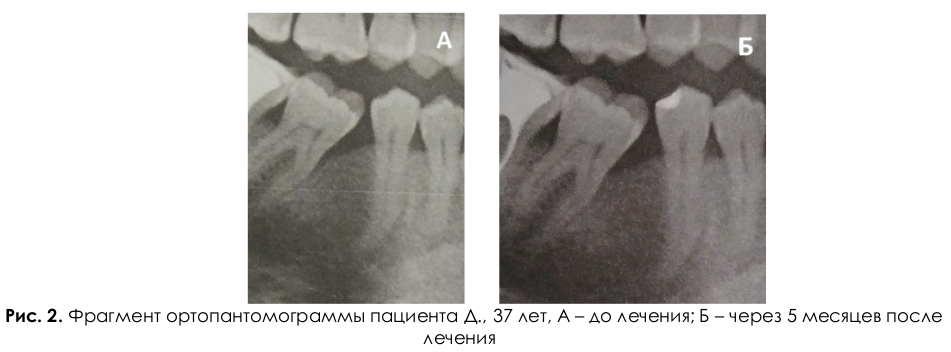

Клинический пример. Пациент Д., 37 лет. Обратился в стоматологическую поликлинику Военномедицинской академии имени С.М. Кирова с жалобами на боль, зуд в дёснах, кровоточивость, подвижность зубов, неприятный запах изо рта. Диагноз: Хронический генерализованный пародонтит средней степени тяжести. Один из карманов диагностировался в области зуба 4.6 (рисунок 2). Пациенту была проведена профессиональная гигиена полости рта с использованием антисептиков. Под местной анестезией было выполнено минимально инвазивное оперативное вмешательство: гингивотомия и кюретаж пародонтального кармана с использованием скейлера, пародонтальных кюрет и экскаваторов. После кюретажа ПК осуществлялось промывание его растворами антисептиков, затем в пародонтальный карман был введен ксеногенный остеопластический материал «Bio-Oss Spongiosa» (Geistlich Pharma) с целью восстановления структуры альвеолярной кости. Последним этапом являлось наложение десневых швов. Была назначена антибактериальная терапия (метронидазол по 0,5 г 2 раза в день курсом 5 суток), десенсибилизирующая терапия (супрастин по 1 таблетке 3 раза в день курсом 5 суток) и противовоспалительная терапия (нимесулид по 1 саше 2 раза в день).

На рентгенограмме до оперативного вмешательства (рисунок 2) визуализируется патологический костный карман, до середины корня зуба 4.6, на рентгенограмме через 5 месяцев (рисунок 3) после оперативного вмешательства отмечается уменьшение размеров костного кармана. Комплексное пародонтологическое лечение продолжается.